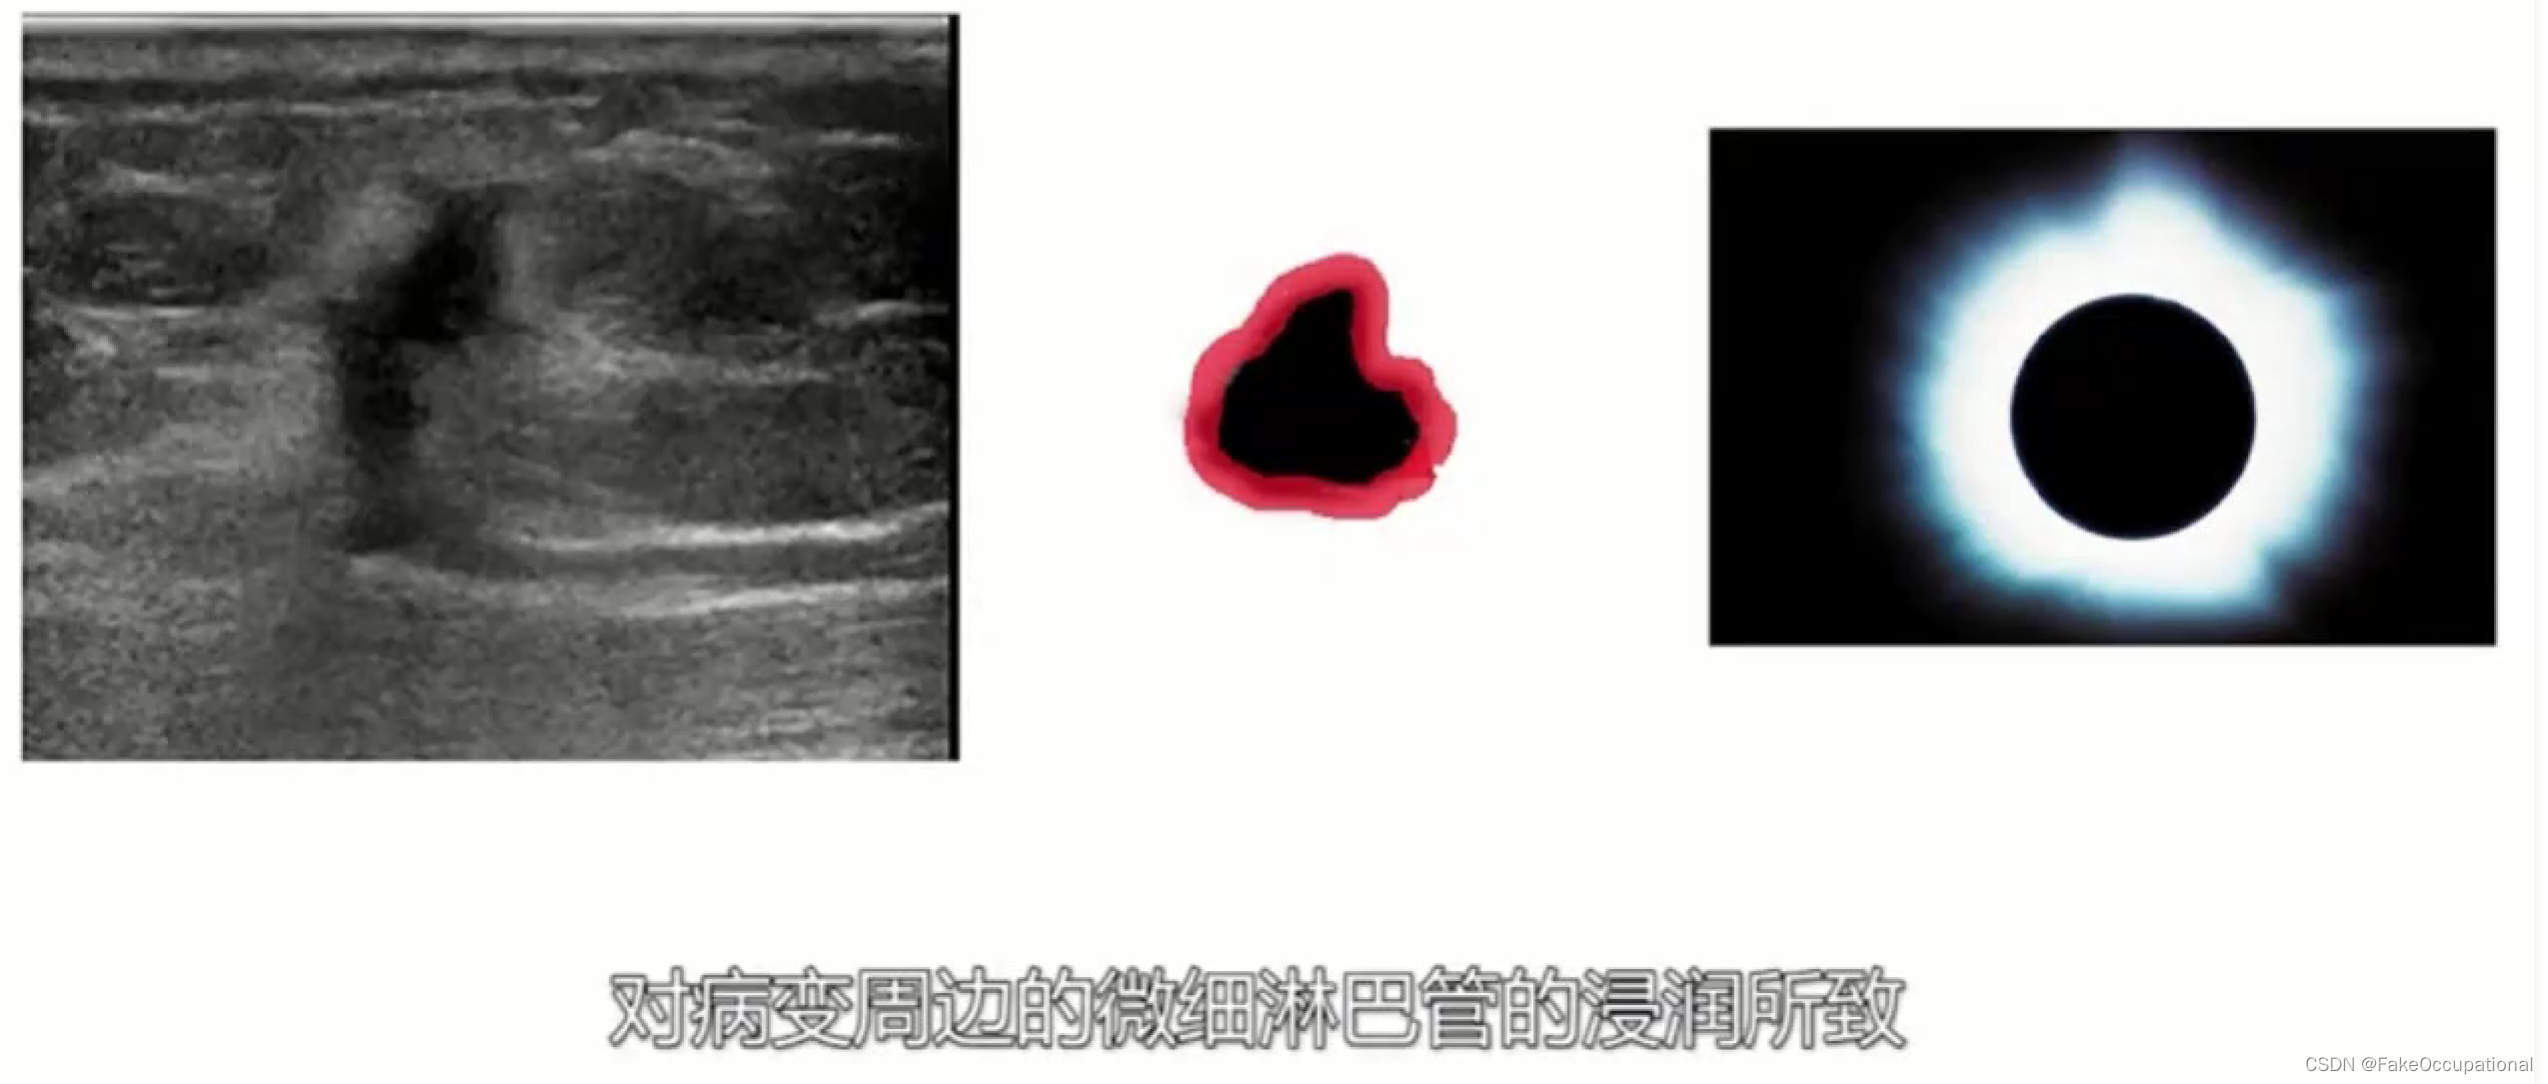

乳腺癌

- 患者18岁,微小癌

- 其理论依据是恶性肿瘤常星离心性生长

- 淋巴结转移